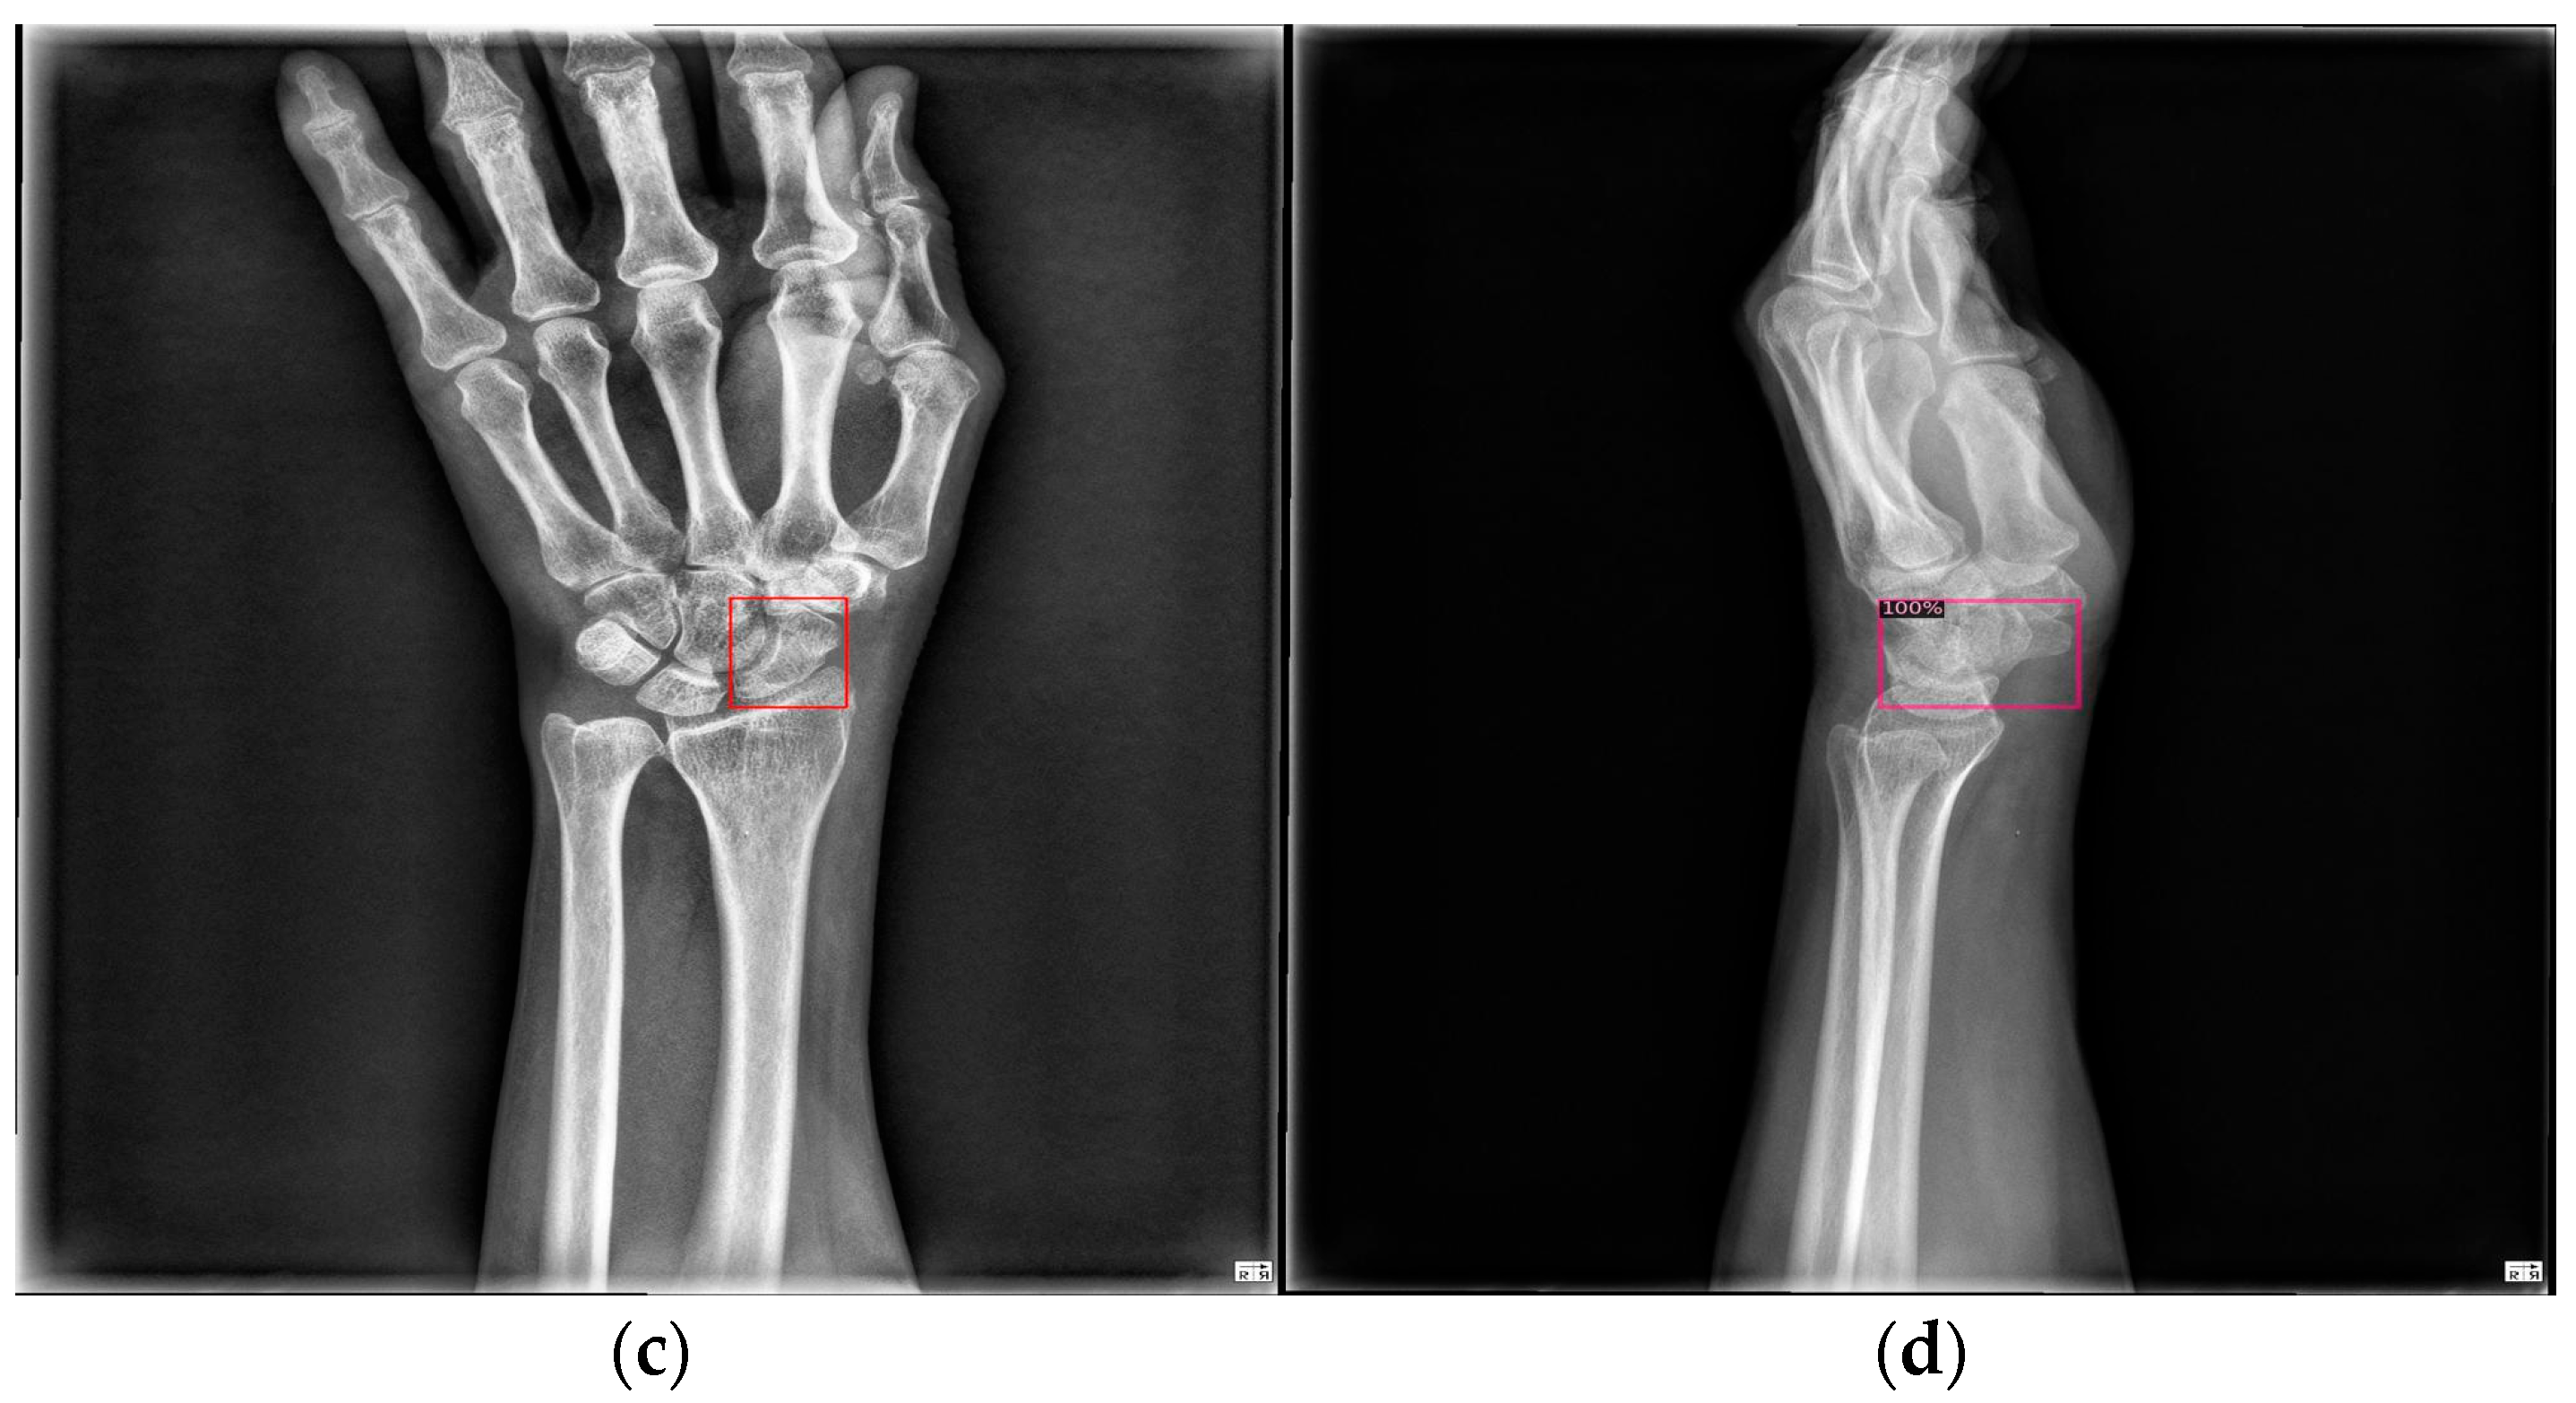

Figure 9 shows the results of scaphoid fracture detection. In the figure, the red area represents the ground-truth box labeled by the doctor, while the green area shows the result predicted by the model. Figure 10 provides an example of a more obvious fracture, whereas Figure 11 illustrates an example of an occult fracture. These examples highlight the challenges in diagnosing scaphoid fractures, as occult fractures are difficult to distinguish by the naked eye. The AP views demonstrate a relatively high IoU, while the LA views also accurately locate the fracture area. This combined approach is effective in drawing the doctor’s attention to the area, enabling quicker identification of the fracture location.

Figure 11.

Occult fracture detection visualization. (a,b) Scaphoid bone slices. The red box is the true answer, and the green box is the predicted result.